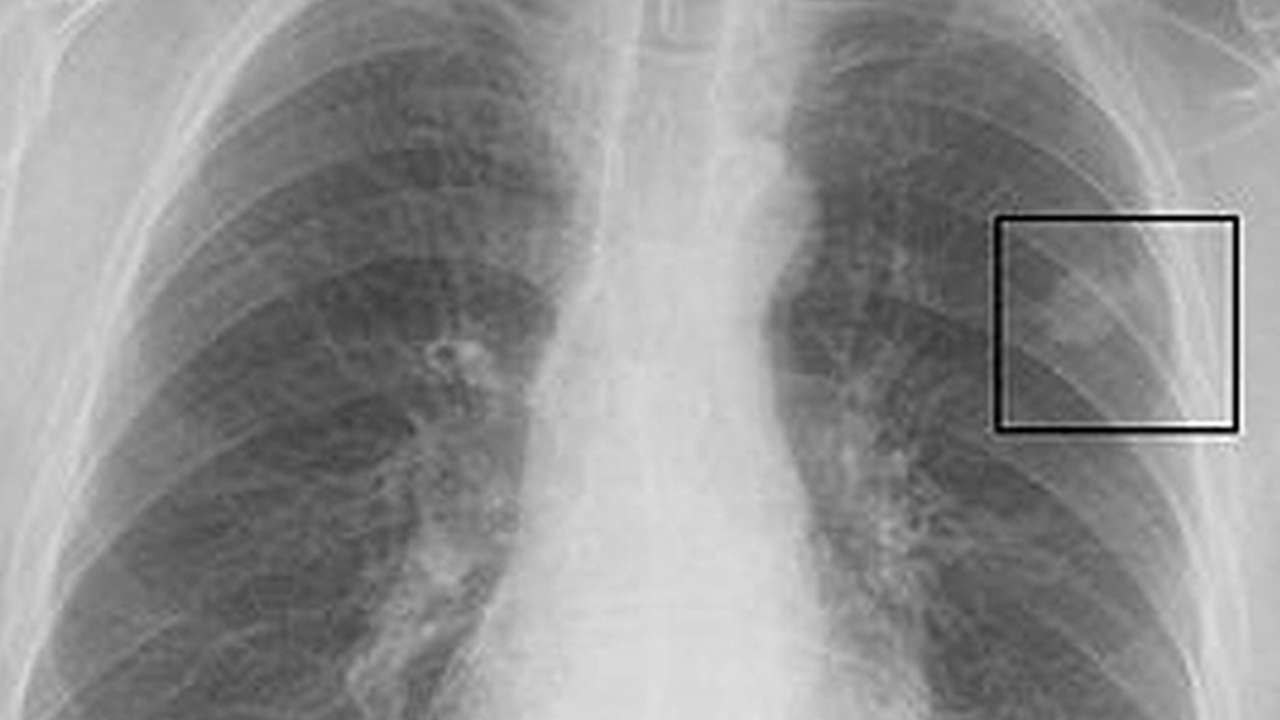

Doç. Dr. Özdemir, akciğer filminde görülen “leke” ifadesinin tıpta “nodül” olarak tanımlandığını belirterek, “Nodül, akciğer dokusundan farklı yapıda ve görüntüde olan alanları ifade eder. Akciğerde nodül oluşmasının birçok sebebi vardır. En sık karşılaşılan nedenler geçmişte geçirilen enfeksiyonlardır. Enfeksiyonlar akciğerde iz bırakabilir ve nodül şeklinde görüntü verebilir” dedi.

Tüm nodüllerin tehlikeli olmadığını vurgulayan Özdemir, asıl önemli olanın büyüme potansiyeli olan nodüller olduğunu söyledi.

“Bizim için risk taşıyan nodüller, zaman içerisinde boyut değiştiren ve büyüme eğilimi gösteren nodüllerdir. Bu nedenle her nodül mutlaka hekim kontrolünde değerlendirilmelidir” diye konuştu.